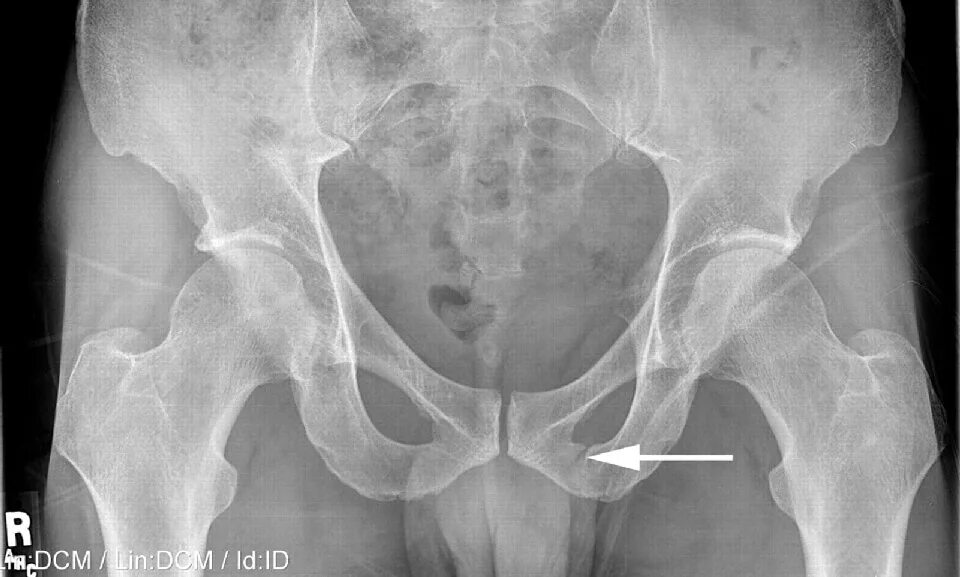

Снимок копчика